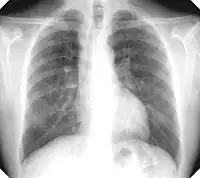

There are three key elements to the diagnosis of silicosis. First, the patient history should reveal exposure to sufficient silica dust to cause this illness. Second, chest imaging (usually chest x-ray) that reveals findings consistent with silicosis. Third, there are no underlying illnesses that are more likely to be causing the abnormalities. Physical examination is usually unremarkable unless there is complicated disease. The examination findings are not specific for silicosis.[19]

For uncomplicated silicosis, chest x-ray will confirm the presence of small (< 10 mm) nodules in the lungs, especially in the upper lung zones. Using the ILO classification system, these are of profusion 1/0 or greater and shape/size "p", "q", or "r". Lung zone involvement and profusion increases with disease progression. In advanced cases of silicosis, large opacity (> 1 cm) occurs from coalescence of small opacities, particularly in the upper lung zones.

With retraction of the lung tissue, there is compensatory emphysema. Enlargement of the hilum is common with chronic and accelerated silicosis. In about 5–10% of cases, the nodes will calcify circumferentially, producing so-called "eggshell" calcification. This finding is not pathognomonic (diagnostic) of silicosis. In some cases, the pulmonary nodules may also become calcified.